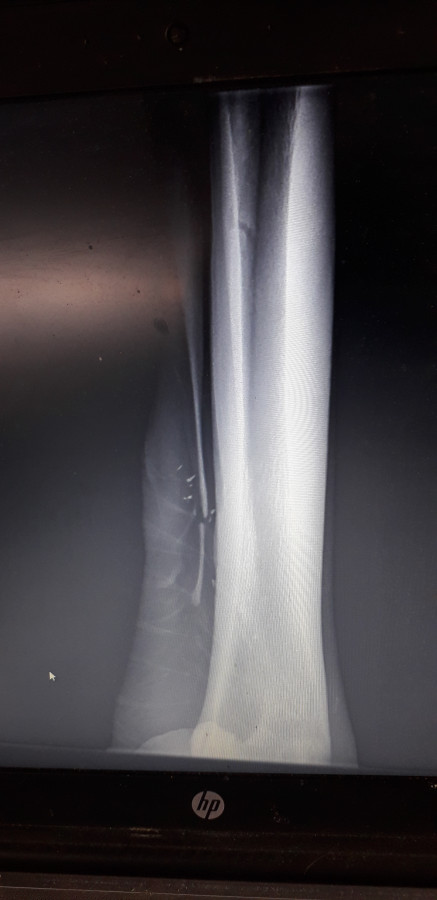

Résultat : même s'il ne boite absolument pas, metatarsien rudimentaire cassé, il va falloir opérer pour retirer le petit bout d'os selon mon vétérinaire. operation simple apparemment nécessitant tout de même 1 mois de box ferme puis 1 mois de sorties courtes en main)

Cliquez pour voir l'image